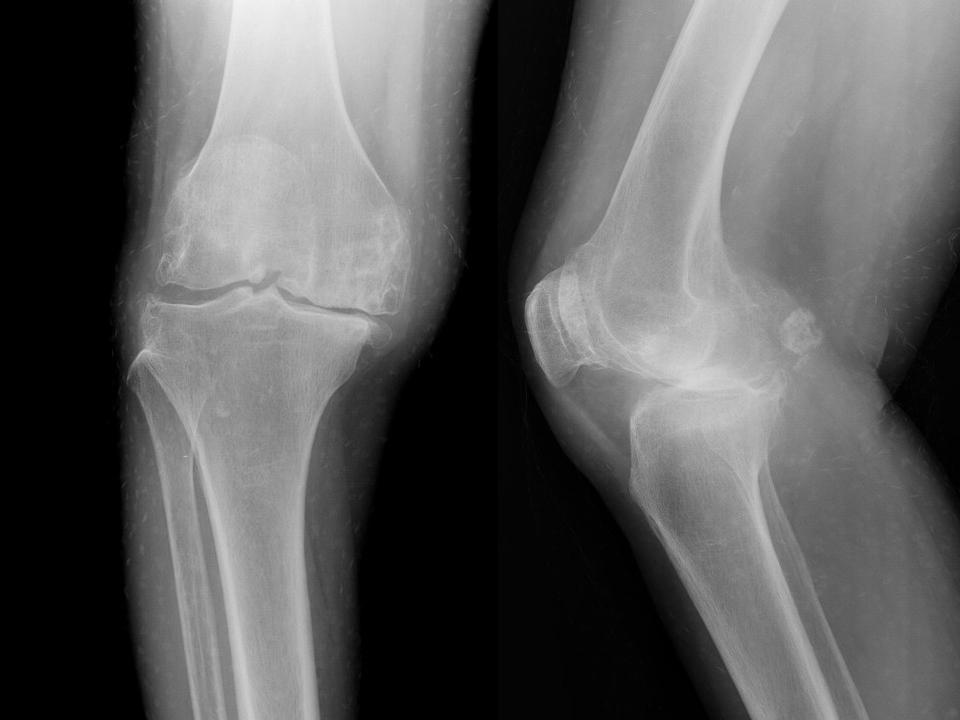

影像学检查 X线 四个方向X线影像 l 早期可无改变 l关节间隙变窄、不均匀、消失(成人<3mm; 老年人<2mm)。 l骨赘形成 l关节内游离体、骨质疏松 l软骨下骨板硬化、囊性变